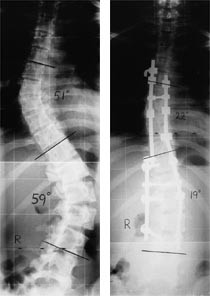

Kurvens størrelse udmåles a.m. Cobb på stående posterior-anterior projektion på lange røntgenfilm. Ved Cobbs metode måles vinklen mellem en linje på overkanten af den hvirvel, der afslutter kurven proksimalt og en linje trukket på underkanten af den hvirvel, der afslutter kurven distalt. Cobbs metode afspejler kun skoliosen i frontalplanet og tager således ikke hensyn til rotationen samt de ændrede kyfose/lordose-vinkler. I sagittalplanet ses typisk øget lændelordose samt delvis udslettet torakalkyfose.

I 1988 introducerede Cotrel & Dubousset CD-instrumentation (18), der er et tostavssystem med flere fiksationspunkter til columna med enten kroge eller pedikelskruer (fig 3). Efter individuel, præoperativ planlægning sker korrektionen af kurven ved såkaldt derotation, hvor man transformerer skoliosen i frontalplanet til en kurve i sagittalplanet, således at den naturlige torakalkyfose og lændelordose genskabes. Gevinsterne ved dette system er, at man undgår den postoperative korsettering samt nedsætter risikoen for udvikling af flat back syndrome .

Resultaterne af den moderne, avancerede skoliosekirurgi er gode korrektioner i alle tre dimensioner; ofte reduceres deformiteten med mere end 70 procent i frontalplanet. Patienter opereret med Harringtonteknik er generelt velfungerende i undersøgelser med op til 20 års followup og tilfredse med det kosmetiske resultat. Mindre neurologiske komplikationer forekommer hos omkring en procent af patienterne, hvorimod total paraplegi er en sjælden komplikation.

Vi tilbyder patienter behandling efter følgende generelle retningslinjer: Spondylodese ved kurver med en Cobbvinkel over 45 grader hos den endnu ikke udvoksede patient og over 50 – 60 grader hos den mature patient. Hos de unge patienter eller patienter med fleksible kurver vælges posterior kirurgi. Hos ældre eller hos patienter med rigide kurver vælges en totrinsprocedure, hvor der først udføres en forreste løsning og herefter en posterior spondylodese. Peroperativt anvendes cellsaver for at begrænse behovet for blodtransfusion, og SEP( somatosensory evoked potentials )- og MEP ( motor evoked potentials )-overvågning af nervefunktionen. Postoperativt bliver patienterne mobiliseret uden korset.